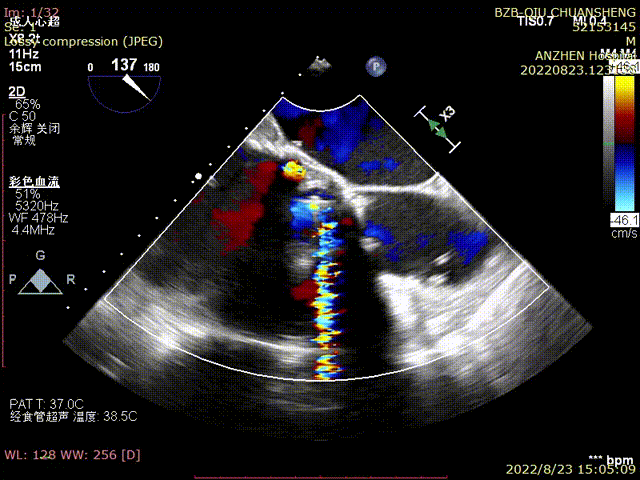

TEE-第二个TAVR后PVL明显减少

TTE-各大瓣膜反流(CDFI)

TTE-左室长轴-二尖瓣生物瓣+主动脉瓣生物瓣(CDFI)